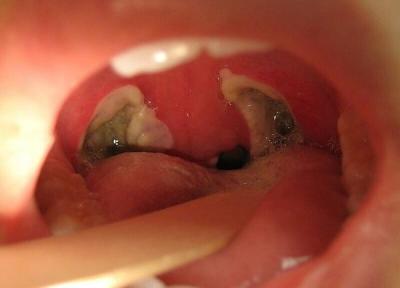

کی باید لوزه های کودک را با جراحی برداشت؟ آیا کودک بعد از جراحی دیگر گلودرد چرکی نمی گیرد؟

پزشکان گاهی در صورتی که کودکی به طور مکرر دچار گلودردهای چرکی ناشی از باکتری استرپتوکوک می شوند، پیشنهاد می کنند که لوزه ها- دو بالشتک بیضی شکل در عقب گلو- با جراحی برداشته شوند.